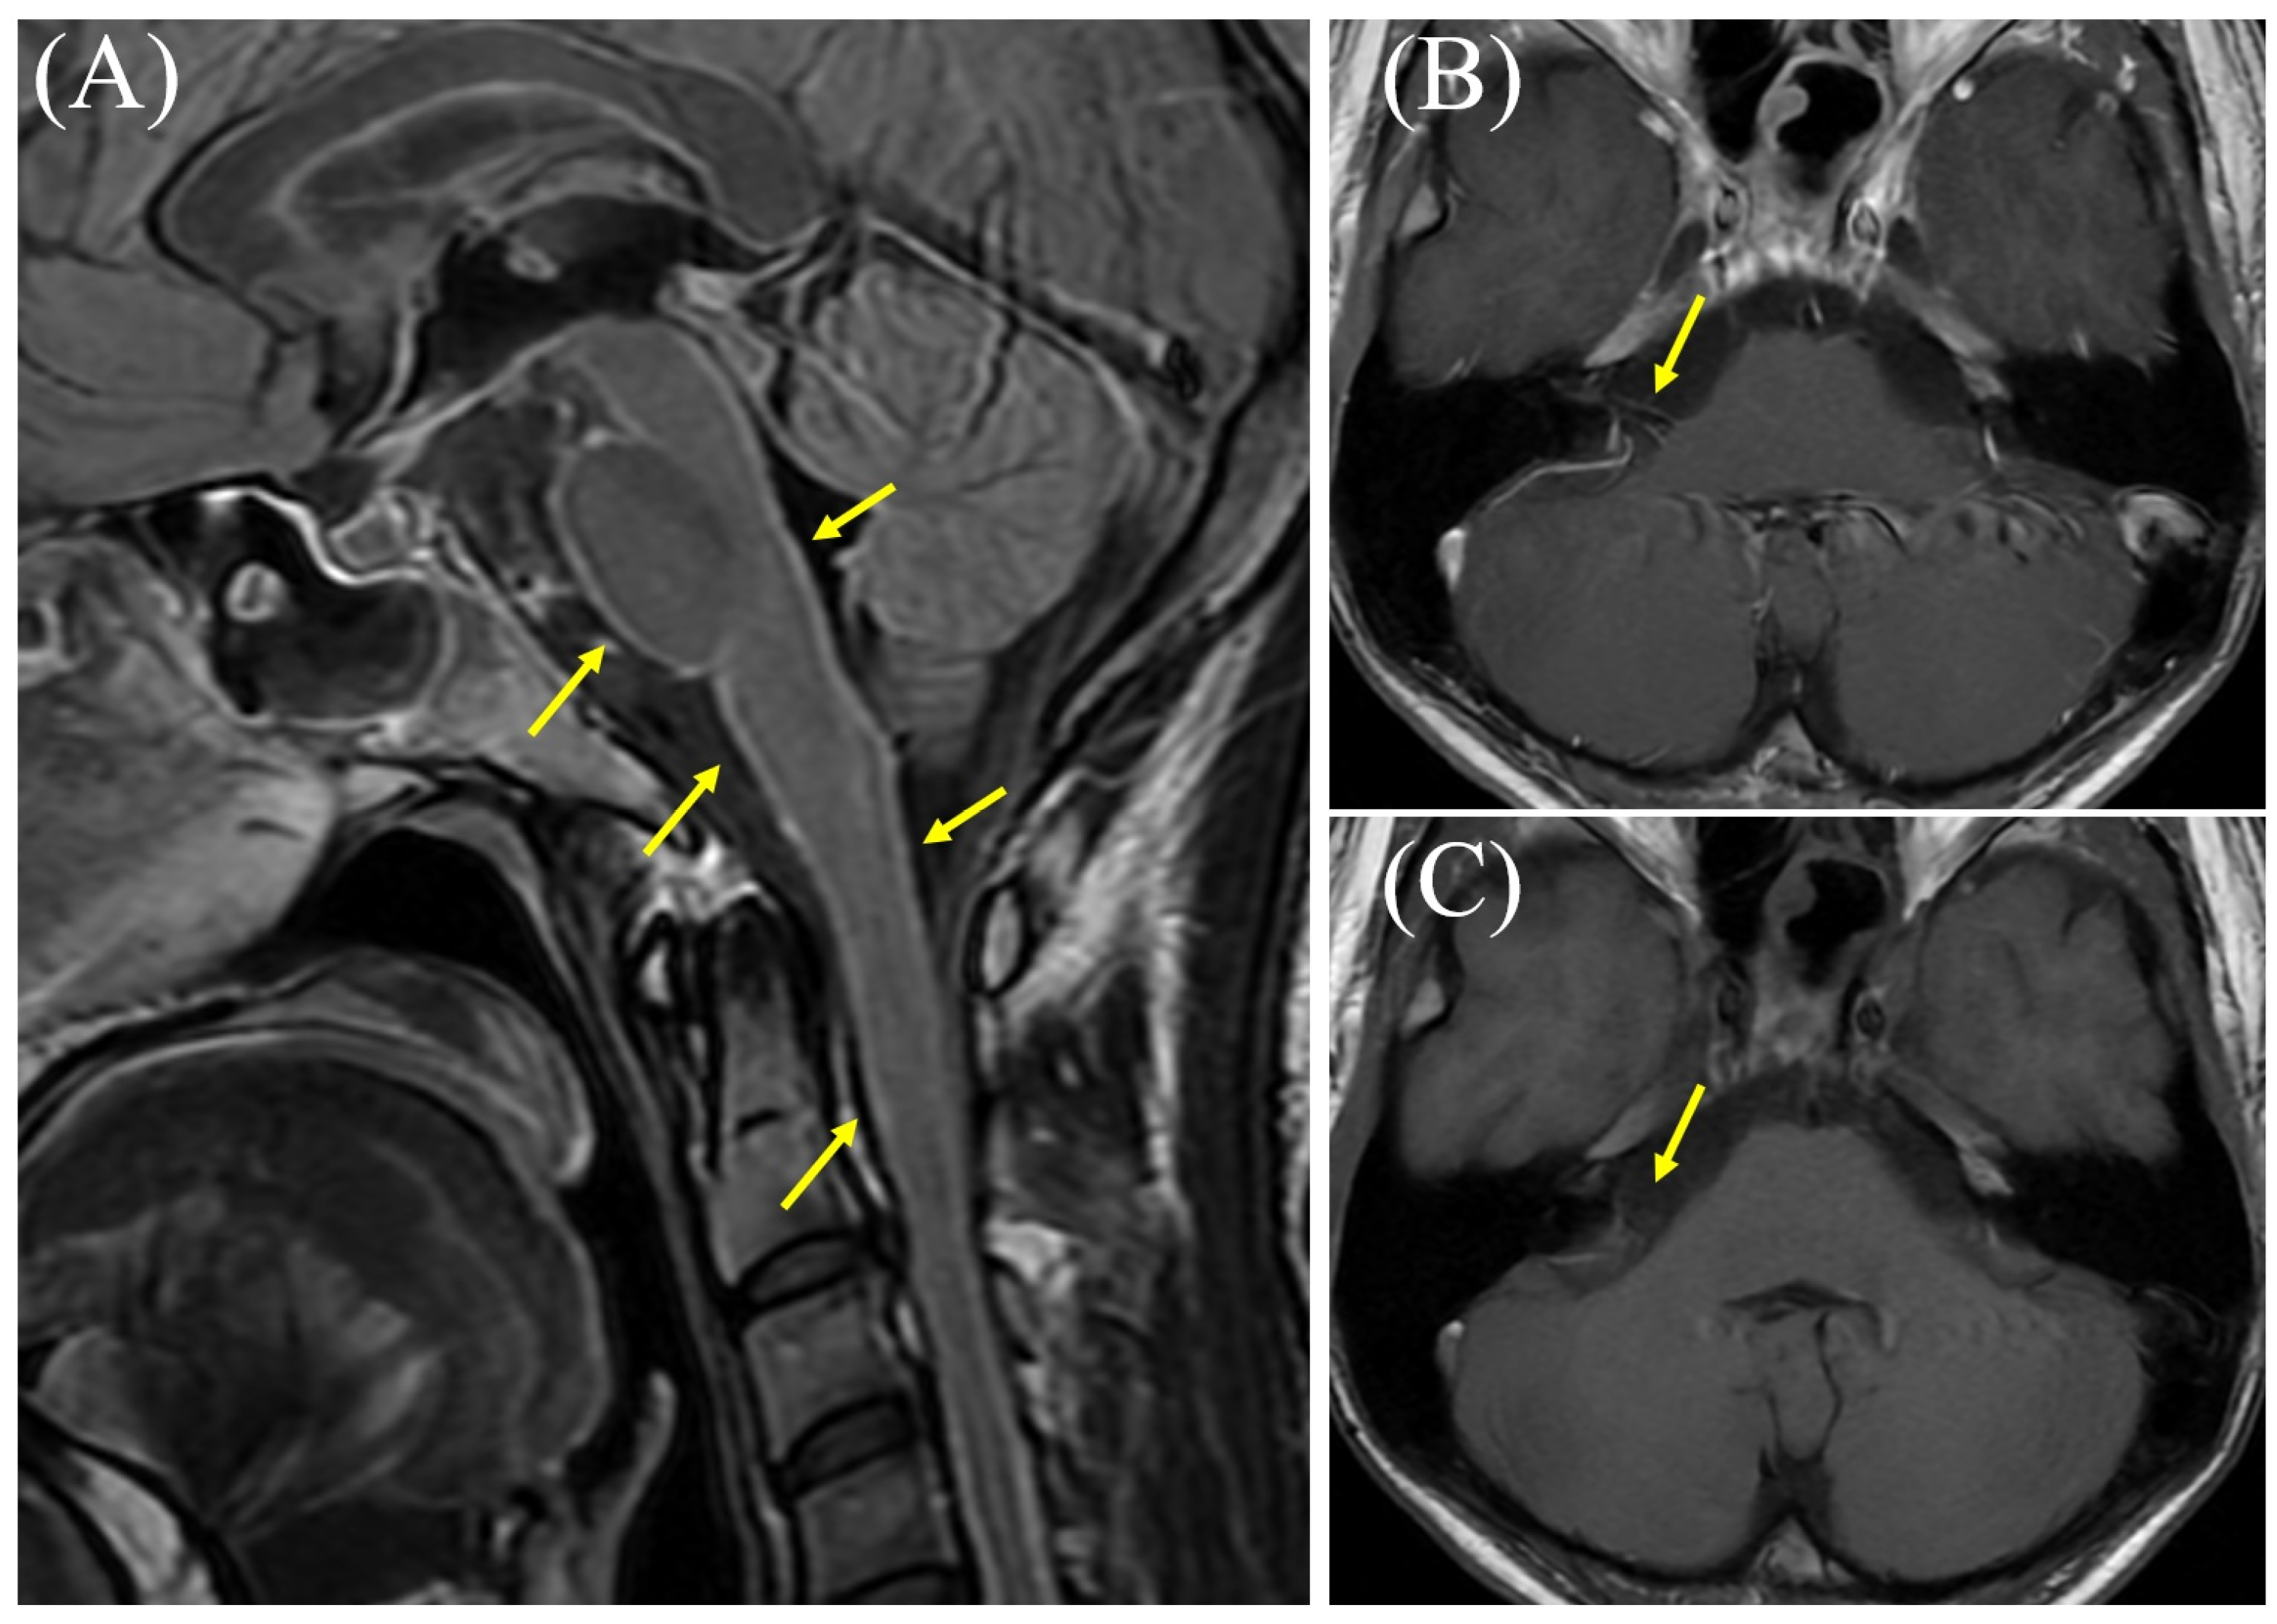

Vestibulocochlear Neuritis as a Paradoxical Reaction in an Immunocompetent Patient with Tuberculous Meningitis

Tsujimoto, S.; Hayashi, K.; Sato, M.; Nakaya, Y.; Miura, T.; Kobayashi, Y. Vestibulocochlear Neuritis as a Paradoxical Reaction in an Immunocompetent Patient with Tuberculous Meningitis. Diagnostics 2025, 15, 3179. https://doi.org/10.3390/diagnostics15243179